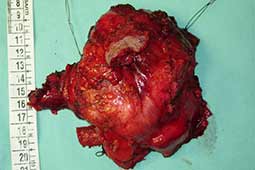

Surgery was performed with curative intent. The patient was positioned supine with the neck fully extended and the head turned away from the tumor. The tumor was approached through the anterior trans-cervical approach described by Dartevelle. This approach allowed us to dissect the subclavian vascular bundle and the nerve roots of the brachial plexus freely, quickly and safely without sacrificing the radical intent of the operation. After assessing the extent of the tumor from inside and outside of the chest, the lateral arches of the first, second and third ribs were cut and removed en-bloc with the surgical specimen (Figure 2). Due to the high risk of de-stabilizing the shoulder girdle after resection of the first three ribs, clavicle division and muscle resection, we reconstructed the chest wall and clavicle using the Stratos™ titanium bars and clips (Strasbourg Thoracic Osteosyntheses System; MedXpert, Heitersheim, Germany) (Figure 3). The chest wall defect and the reconstructed clavicle were covered with polytetrafluoroethylene (PTFE) patches (Figure 4).